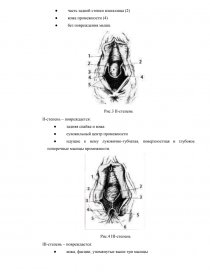

Проблема родового травматизма у женщин, перенесших роды через естественные родовые пути, является важной проблемой современного акушерства. Повреждение во время родов, особенно первородящих, – довольно частое осложнение.Травматизация мягких тканей родового канала наблюдается у каждой 3 - 5-й роженицы. Разрыв промежности – это разрыв кожи и других структур мягких тканей, которые у женщин отделяют влагалище от заднего прохода. Разрыв промежности в основном возникает у женщин в результате вагинальных родов, которые напрягают промежность. Это наиболее распространенная форма акушерской травмы. Разрыв промежности отличается от эпизиотомии, при которой промежность намеренно разрезается, чтобы облегчить доставку. Согласно литературным данным травмы родовых путей (разрывы шейки матки, стенок влагалища, промежности и вульвы) составляют до 40 % случаев, у первородящих они встречаются в 73 % случаев, а при акушерских операциях (наложение акушерских щипцов, вакуум-экстратора и др.) достигают 90 %. Разрывы промежности III степени колеблются от 0,4 до 5 %.

Акушерские травмы промежности наблюдаются достаточно часто и обусловлены множеством причин. Предрасполагают к разрыву промежности половой инфантилизм, высокая промежность, рубцовые изменения тазового дна после предшествующих травм в родах или пластических операций. Наступлению разрыва промежности так же могут способствовать крупные размеры головки, неправильное ее вставление, наличие предшествующих разрывов промежности.